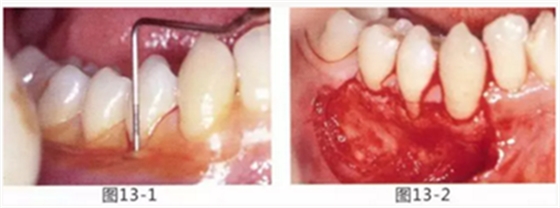

由于口腔前庭較淺且沒有附著齦,使菌斑容易滯留且刷牙困難的病例

圖13-1 使用碘溶液進行染色,頰側基本看不到角化牙齦,且無口腔前庭的狀態(tài)。

圖13-2 為了擴張口腔前庭,獲取附著齦而進行了游離齦移植術。受皮床一定不能發(fā)生移動,盡可能使厚度均等。

圖13-3 手術剛結束的狀態(tài)。通過骨膜縫合的褥式縫合將移植片固定,使其無法移動。

圖13-4 手術完成2年后的狀態(tài)。口腔前庭得到擴張,即使正在進行正畸治療,也沒有妨礙到清潔。